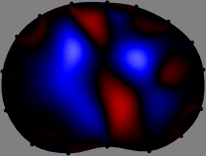

The sensitivity matrix is pre-computed assuming a homogeneous conductivity distribution in the imaging plane (Fig. 2). The numbers of rows and columns of are 208 and , respectively. For simplicity, we used a 2D forward model of the cross-section to compute . The th column of comprises the changes in the voltage data subject to a unit conductivity change in the th pixel .

To explain the FER method, we closely examine the correlations among column vectors of the sensitivity matrix , described in Fig. 2. The correlation between and can be expressed as

for [23]. This shows that the column vector is like an EEG (electroencephalography) data induced by dipole sources with directions at locations . Given that two dipole sources at distant locations produce mutually independent data, the correlation between and decreases with the distance between and . Fig. 2 shows a few images of the correlation as a function of for four different positions . The correlation decreases rapidly as the distance increases. In the green regions where the correlation is almost zero, is nearly orthogonal to .

Fig. 2 shows that if and are far from each other, the corresponding columns of the sensitivity matrix are nearly orthogonal. This somewhat orthogonal structure of the sensitivity matrix motivates an algebraic formula that directly computes the local ensemble average of conductivity changes at each point using the inner product between changes in the data and a scaled sensitivity vector at that point: